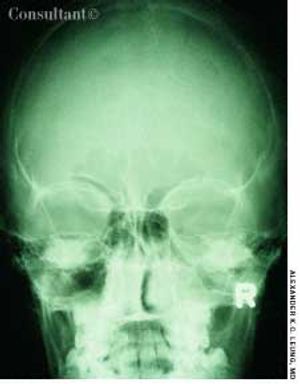

A 10-year-old boy had a headache, fever, cough, and nasal discharge for 2 days. His temperature was 38°C (100.4°F). Mucopurulent, yellow nasal discharge, fetid breath, and tenderness over the maxillary area were noted.